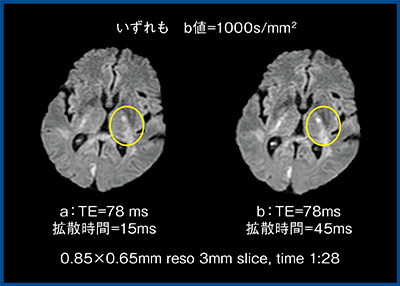

図4は,いずれもb=1000s/mm2,TE=78msで拡散時間のみ15msと45msに変化させた画像である。左内包の周囲のコントラストは,拡散時間=45ms(図4b)の方が明瞭であることがわかる。ZGOのように高いGmaxを備えることで,初めて拡散時間を短く設定することができ,このような比較が可能となる。従来装置では,拡散時間が極端に短くなるような撮像はできなかったため意識されていないが,拡散時間もコントラストを変える要因となる。

近年,本来はDWIで高信号となるべき転移病変や脳梗塞が描出されなかったということが,高性能MRIにて散見されるのは拡散時間が短いためである。そのため,今後は至適TEおよび拡散時間の検討が必要であると考える。

図4 DWIにおける拡散時間の影響